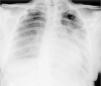

Case reportA 14-year-old girl with a history of hemiplegic migraine and pineal cyst was admitted for control brain magnetic resonance imaging (MRI). During anesthesia induction with propofol she suffered bradycardia, which was reversed with atropine, followed by ventricular tachyarrhythmia, reversed with lidocaine and precordial thump. Within hours she developed pulmonary edema (Figure 1) and global respiratory failure (PaO2/FiO2 156, pCO2 57 mmHg) and hypotension (systolic/diastolic blood pressure 89/56 mmHg). The transthoracic echocardiogram showed a dilated left ventricle with global hypokinesia of the mid and basal segments but sparing the apex, resulting in moderate to severe impairment of left ventricular global systolic function and reduced ejection fraction (<30%) (Figures 2 and 3). The electrocardiogram (ECG) showed persistent sinus tachycardia and nonspecific ST-T wave abnormalities in V4 and V5 (Figure 4). Cardiac biomarkers were elevated (total creatine kinase [CK] 217 UI/l, troponin I 2.42 ng/ml and pro-brain natriuretic peptide [proBNP] 8284 pg/ml). The patient was placed on diuretics and captopril, with dopamine to optimize renal function (maximum 2 μg/kg/min) and digoxin in the first 24 h.